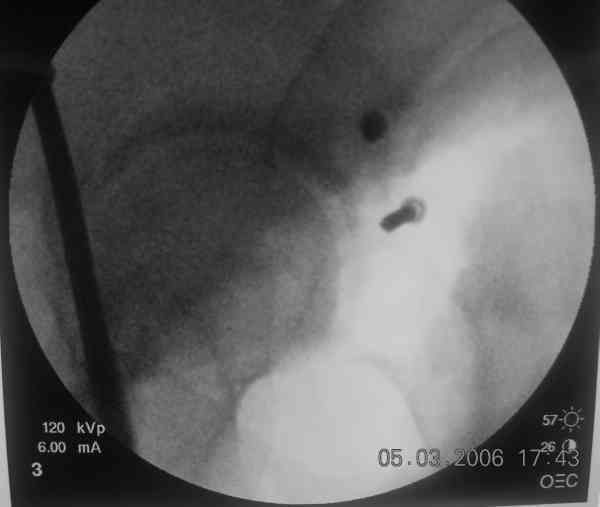

The 2nd example is of a motorcyclist with a transverse fracture-dislocation...he had a closed attempted reduction and placed in traction but the manipulative reduction was not concentric (not unusual for this injury pattern)...so the traction was adjusted to be just enough to disengage the head from the fracture (12#) until he could be cleared for surgery one day after injury...he was treated "urgently" then with a prone KL, clean the fracture, reduce and clamp it, screw it, support with a balanced plate, close, and enjoy...2-3hours, 400cc EBL, blah, blah, blah..

Here's a pic from the foot of the bed and you can see the clamp in the wound and the knee is extended so he must've had a tight rectus. The C-arm is rolled back to an obturator oblique image to reveal the anterior column...we put a slight outlet tilt to combine the images and give a better view of the anterior column...we can see the posterior column limb reduction in the wound, we can palpate the quadrilateral surface limb, and the image demonstrates the anterior column portion...you can adjust the tilt and rotation to image tangentially to the fracture plane if you'd like. We've inserted a 2mm K wire to site the starting point and aim/orientation for the drill and screw

Prone Imaging

same image, just another look.

Prone Inlet

OK, now we're inserting the drill percutaneosuy using a sleeve. This fluoro shot is not for this patient (notice no clamp) but I was too lazy to go searching the PACS for one with the clamp on, so pretend...I'll save the next ones and send along...the imaging is the same and the clamp doesn't obstruct imaging other than very rarely...you can always tilt the C-arm a bit to clear it if the clamp obstructs the exact spot that you'd like to see. We'll assume that everyone knows the safe zone for a medullary ramus screw. Use a calibrated drill and sleeve of known length to simplify your life...or use Alex's fancy cannulated screws...I like 3.5mm screws because the oscillating 2.5mm drill bounces and remains intraosseus when it oscillates and contacts endosteal cortical ramus... so will the screw, and like a long bent screw IF the fracture is clamped... if unclamped, when the screw contacts the endosteum, it pushes the reduction apart instead of bouncing. The big 7mm cannulated screws fit few patients and extrude...we very rarely use them any more...you'll see an old one later.

Prone Obturator-Outlet

Screw insertion using the obturator-outlet combination image.

12.Prone Obturator-Outlet

Same with a contoured pelvic reconstruction plate applied and tensioned.

Prone Iliac Oblique

The other oblique reveals the extra-articular implants.... you know the AC screw is extra-articular from the other views.